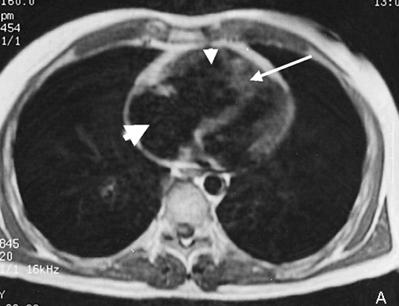

Imagine Rx. de profil cu HVD Aspect CT de HTP primara